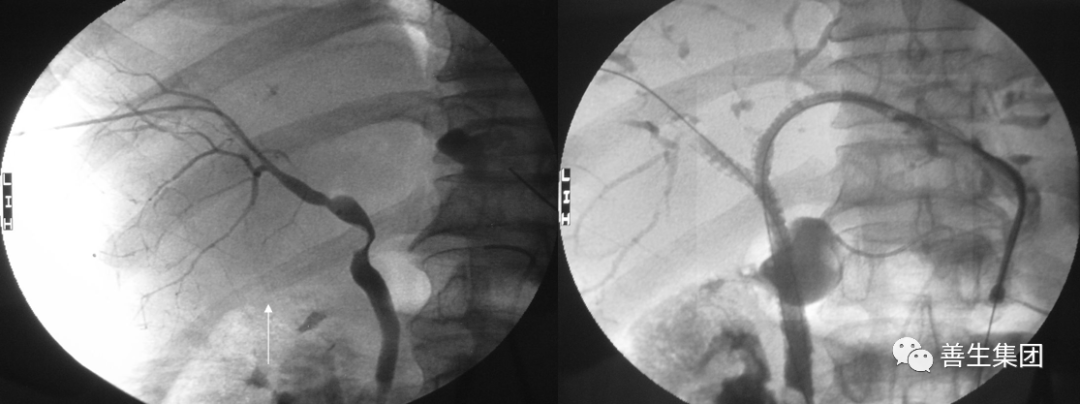

高位梗阻PTC示肝门部梗阻,左右肝管分别受侵犯

胆管支架什么样子经皮肝胆管穿刺置管引流术(PTCD)及胆道内支架临床应用_https://www.jmylbn.com_新闻资讯_第9张

高位梗阻胆管癌患者

胆管支架什么样子经皮肝胆管穿刺置管引流术(PTCD)及胆道内支架临床应用_https://www.jmylbn.com_新闻资讯_第10张

穿刺右肝管分别穿刺左右肝管,Y型放置2枚支架型内支架

胆管支架什么样子经皮肝胆管穿刺置管引流术(PTCD)及胆道内支架临床应用_https://www.jmylbn.com_新闻资讯_第11张